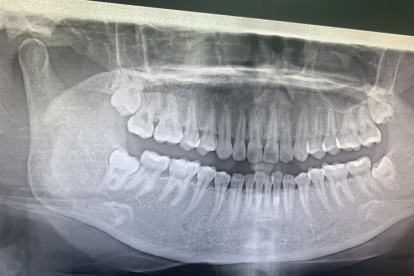

阻生智齿可能因生长空间不足引起,伴随张口受限症状。可采用牙龈瓣切除术解除冠周盲袋,完全埋伏的智齿需行骨开窗拔除术。手术前后需配合抗生素预防感染。根据智齿位置和炎症程度选择合适术式。